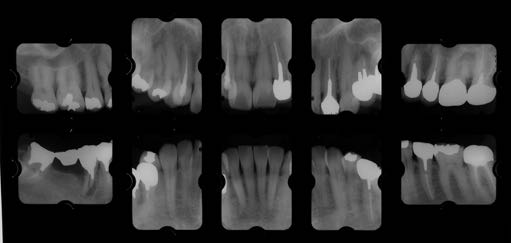

治療後01

治療後02

治療後03

治療後04

治療後05